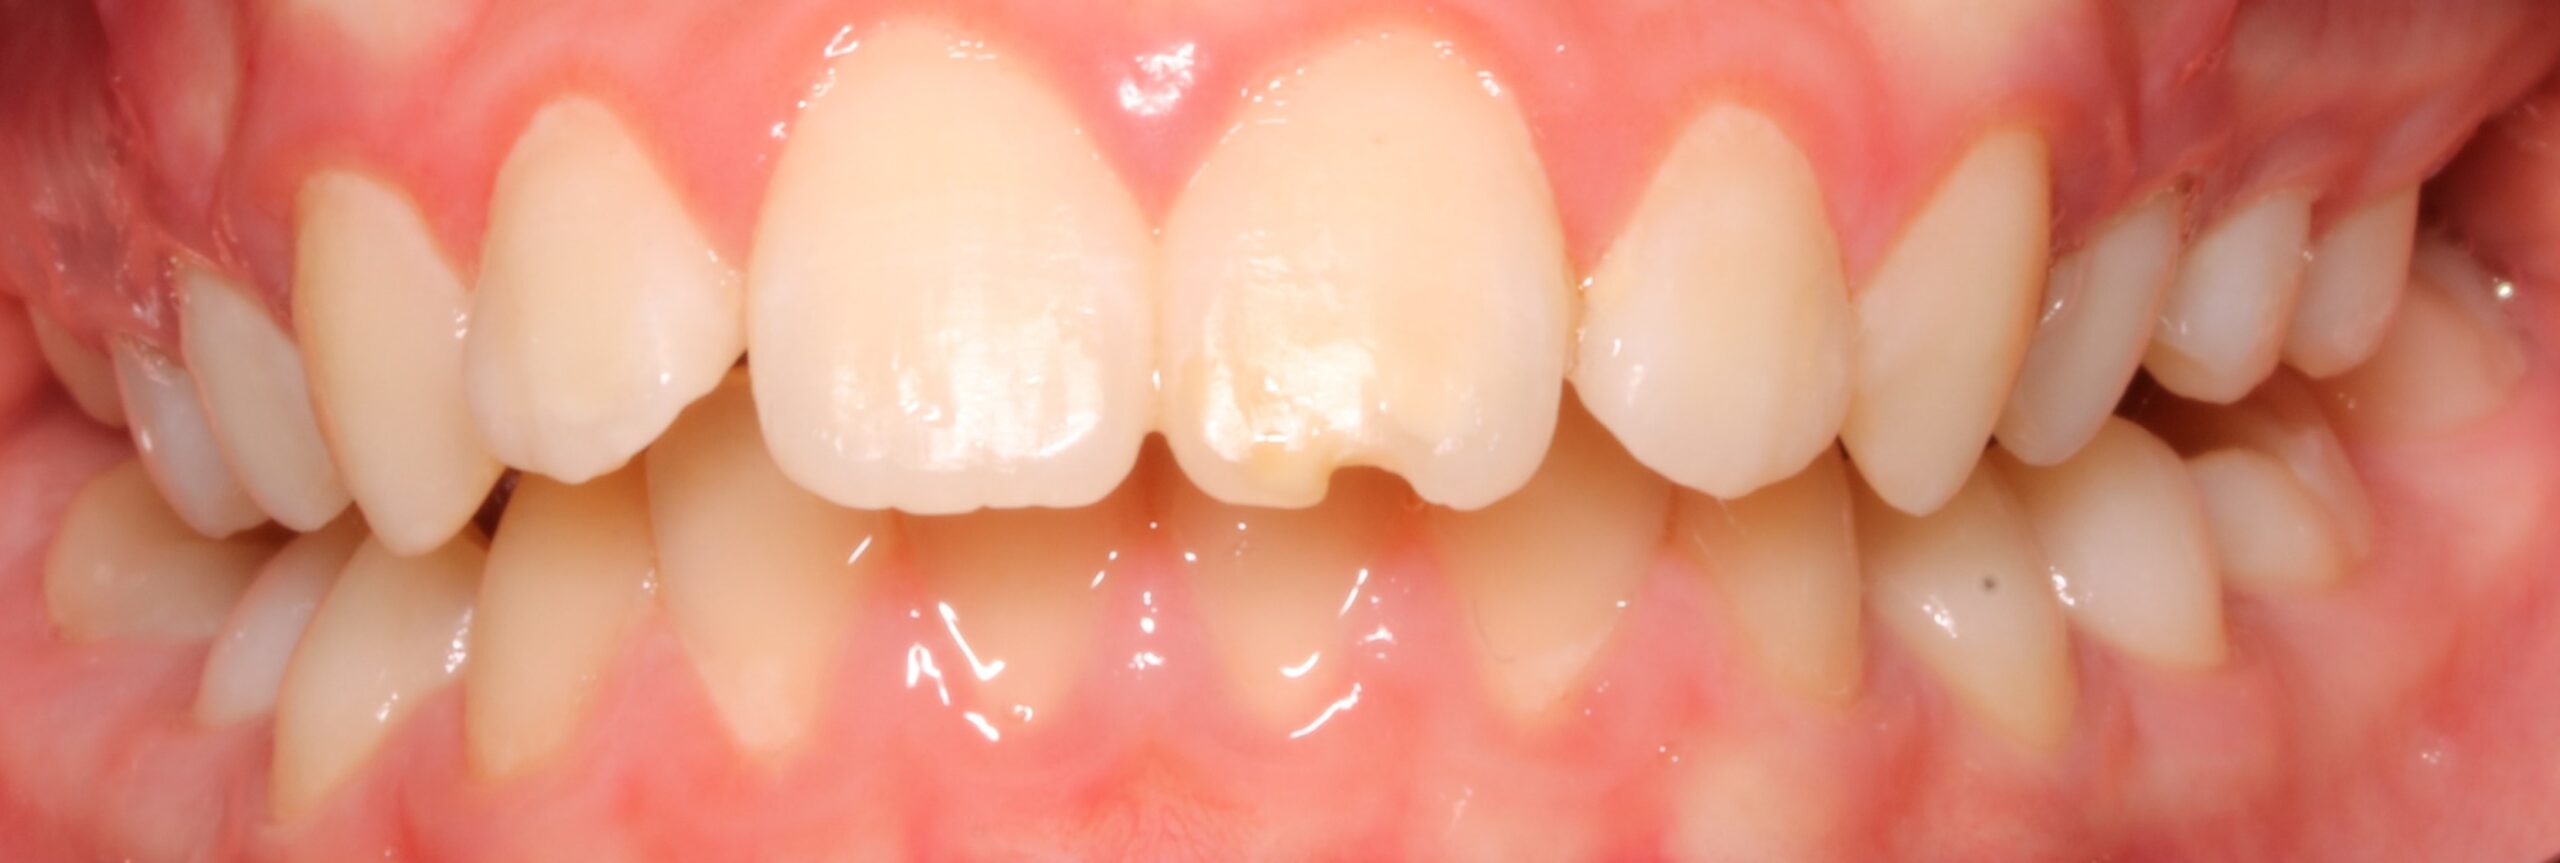

BORDE IRREGULAR EN 21 RECONSTRUCIÓN AL FINAL DE TRATAMIENTO